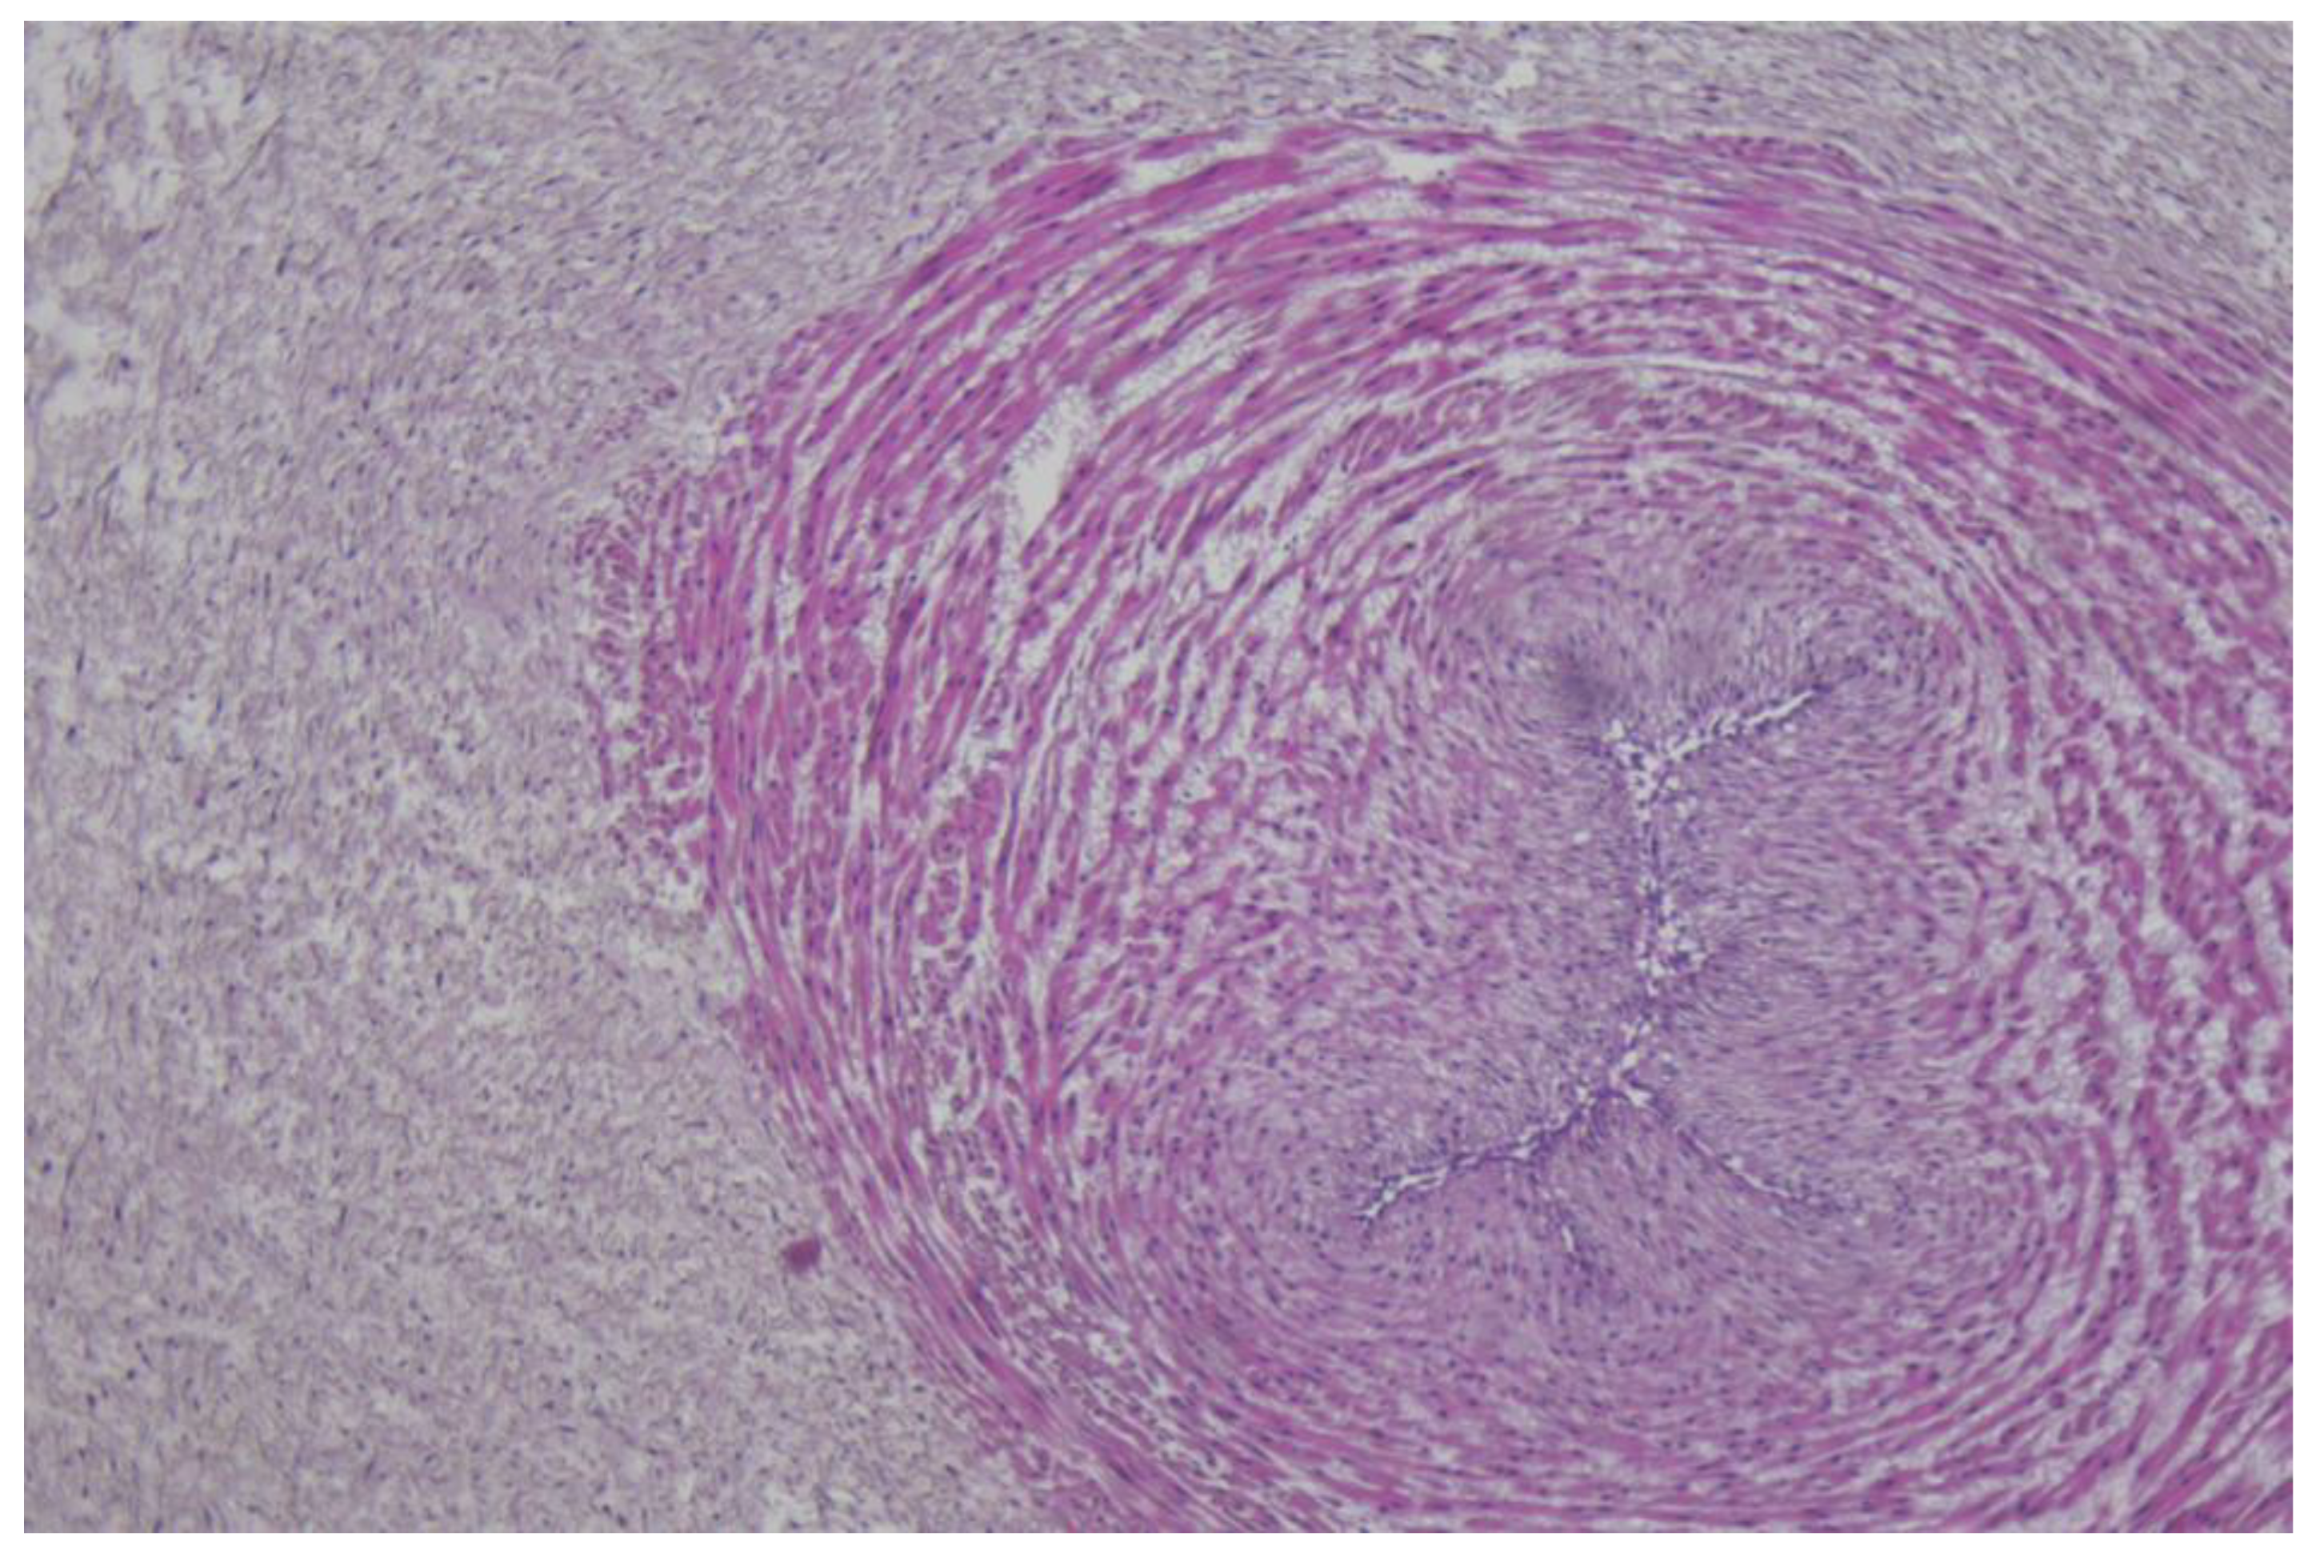

- Resta, L.; Vimercati, A.; Cazzato, G.; Fanelli, M.; Scarcella, S.V.; Ingravallo, G.; Colagrande, A.; Sablone, S.; Stolfa, M.; Arezzo, F.; et al. SARS-CoV-2, Placental Histopathology, Gravity of Infection and Immunopathology: Is There an Association? Viruses 2022, 14, 1330. [Google Scholar] [CrossRef] [PubMed]